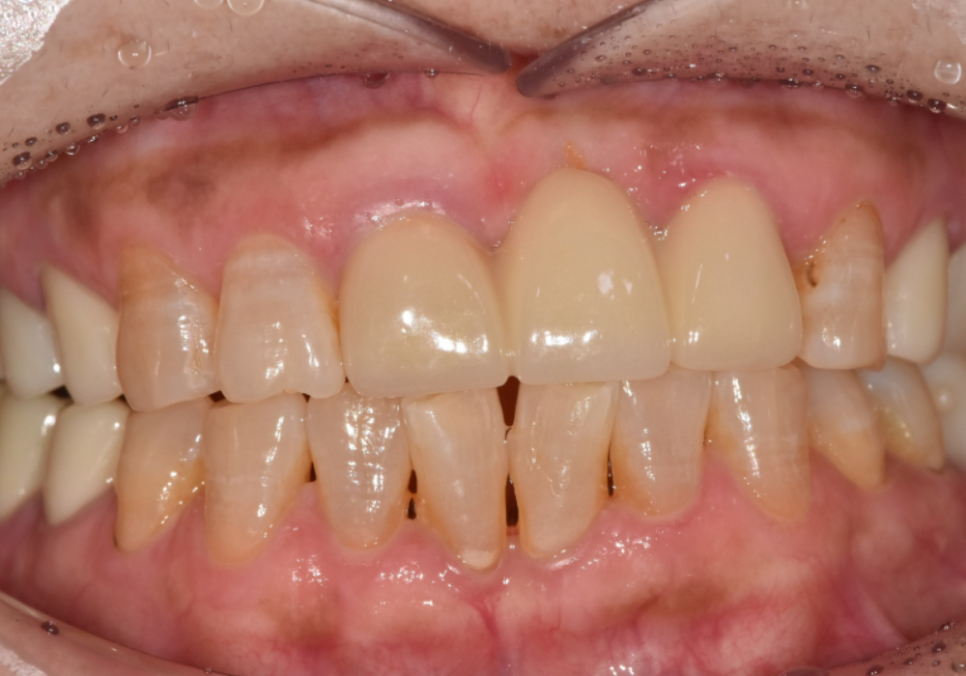

왜 이분은 교정 대신 라미네이트를 선택했을까요?

삐딱하게 뻗은 '나비 모양 앞니', 교정 없이 하루 만에 바뀔 수 있을까?

최근 아래 앞니가 나비 날개처럼 뻗어

고민이셨던 분이 찾아오셨습니다.

치아가 바깥으로 벌어져 있다 보니

평소 입술이 자꾸 걸리고

면 요리를 드실 때도 잘 끊기지 않아

무척 불편하셨다고 해요.